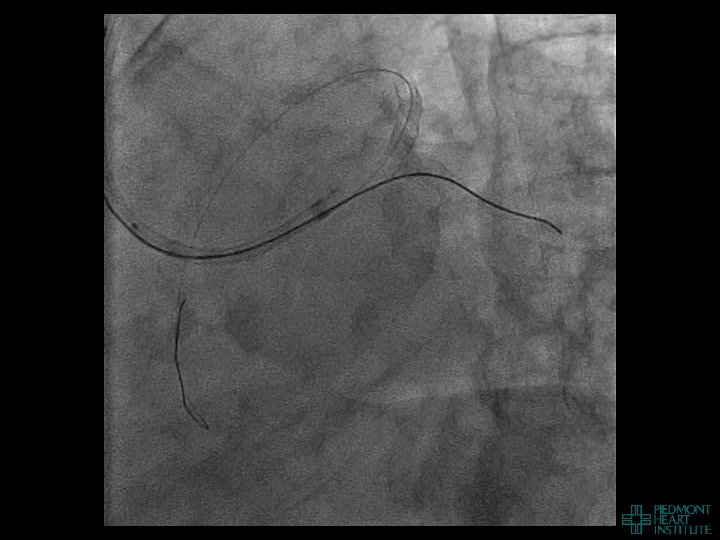

Coronary Perforation Methods of Patient Management • Dual Catheter (‘Ping Pong’) Technique • Prolonged

Coronary Perforation Methods of Patient Management • Dual Catheter (‘Ping Pong’) Technique • Prolonged balloon inflation and covered stents • Reversal of anticoagulation — Know contradictions to protamine sulfate for UFH; Avoid bivalirudin, LMWH — Reserve GP 2 b 3 a inhibition until successful crossing and wire change-out Embolization • — Coil, gelfoam, methacrylate, autologous blood/fat • Microcatheter Occlusion • Confirmation of successful management — Contralateral injection — Right heart catheterization — Echocardiogram — Contrast echocardiography

Case Example 4

Case Example 5